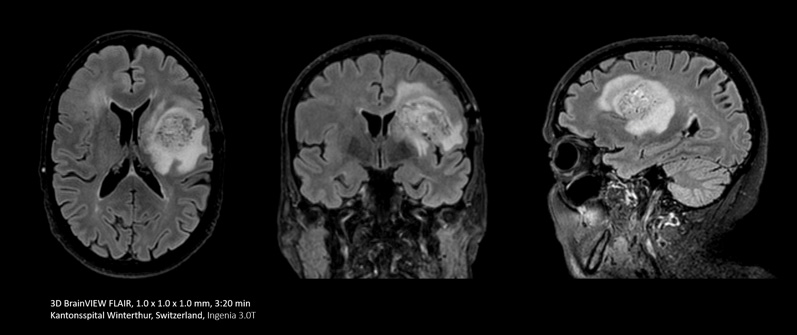

Bei einigen Untersuchungen, beispielsweise von Gehirn und Wirbelsäule, lässt eine hohe räumliche Auflösung sehr kleine Nerven und Gefäße besser erkennen. Um diese Auflösung zu erreichen, können mit Compressed SENSE 2D-MR-Scansequenzen durch schnellere 3D-Sequenzen ersetzt werden.

Mit Compressed SENSE lässt sich ein 2D-FLAIR-Scan mit einer Ausrichtung durch einen volumetrischen 3D-FLAIR-Scan mit mehreren Ausrichtungen ersetzen. Die Scandauer beträgt dabei lediglich dreieinhalb Minuten.

Ich erstelle häufig Bilder des Gehirns. Bisher haben wir die FLAIR-Sequenz mit einer Schichtdicke von 5 mm verwendet. Mit Compressed SENSE können wir jetzt einen volumetrischen 3D-Scan statt in sechs Minuten in etwa dreieinhalb Minuten durchführen.“

Dr. Mark Oswood, MD, PhD, Neuroradiologe, Hennepin Healthcare, Minneapolis, USA